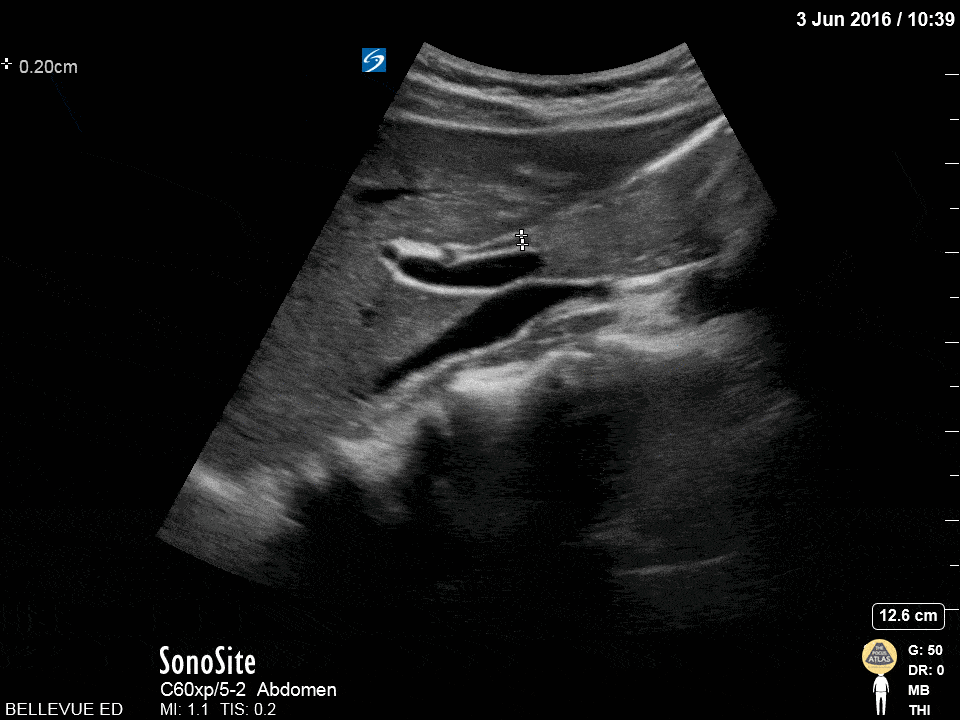

Biliary - Olive Sandwich

Caption

The “olive sandwich” sign: the small round hepatic artery (in cross section) sandwiched between long axis views of the CBD superiorly and portal vein inferiorly. The IVC is seen in long axis deep to the portal vein. Hannah Kopinksi and Dr. Lindsay Davis - NYU Emergency Medicine